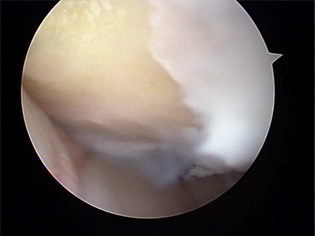

미세천공술 1

미세천공술 2